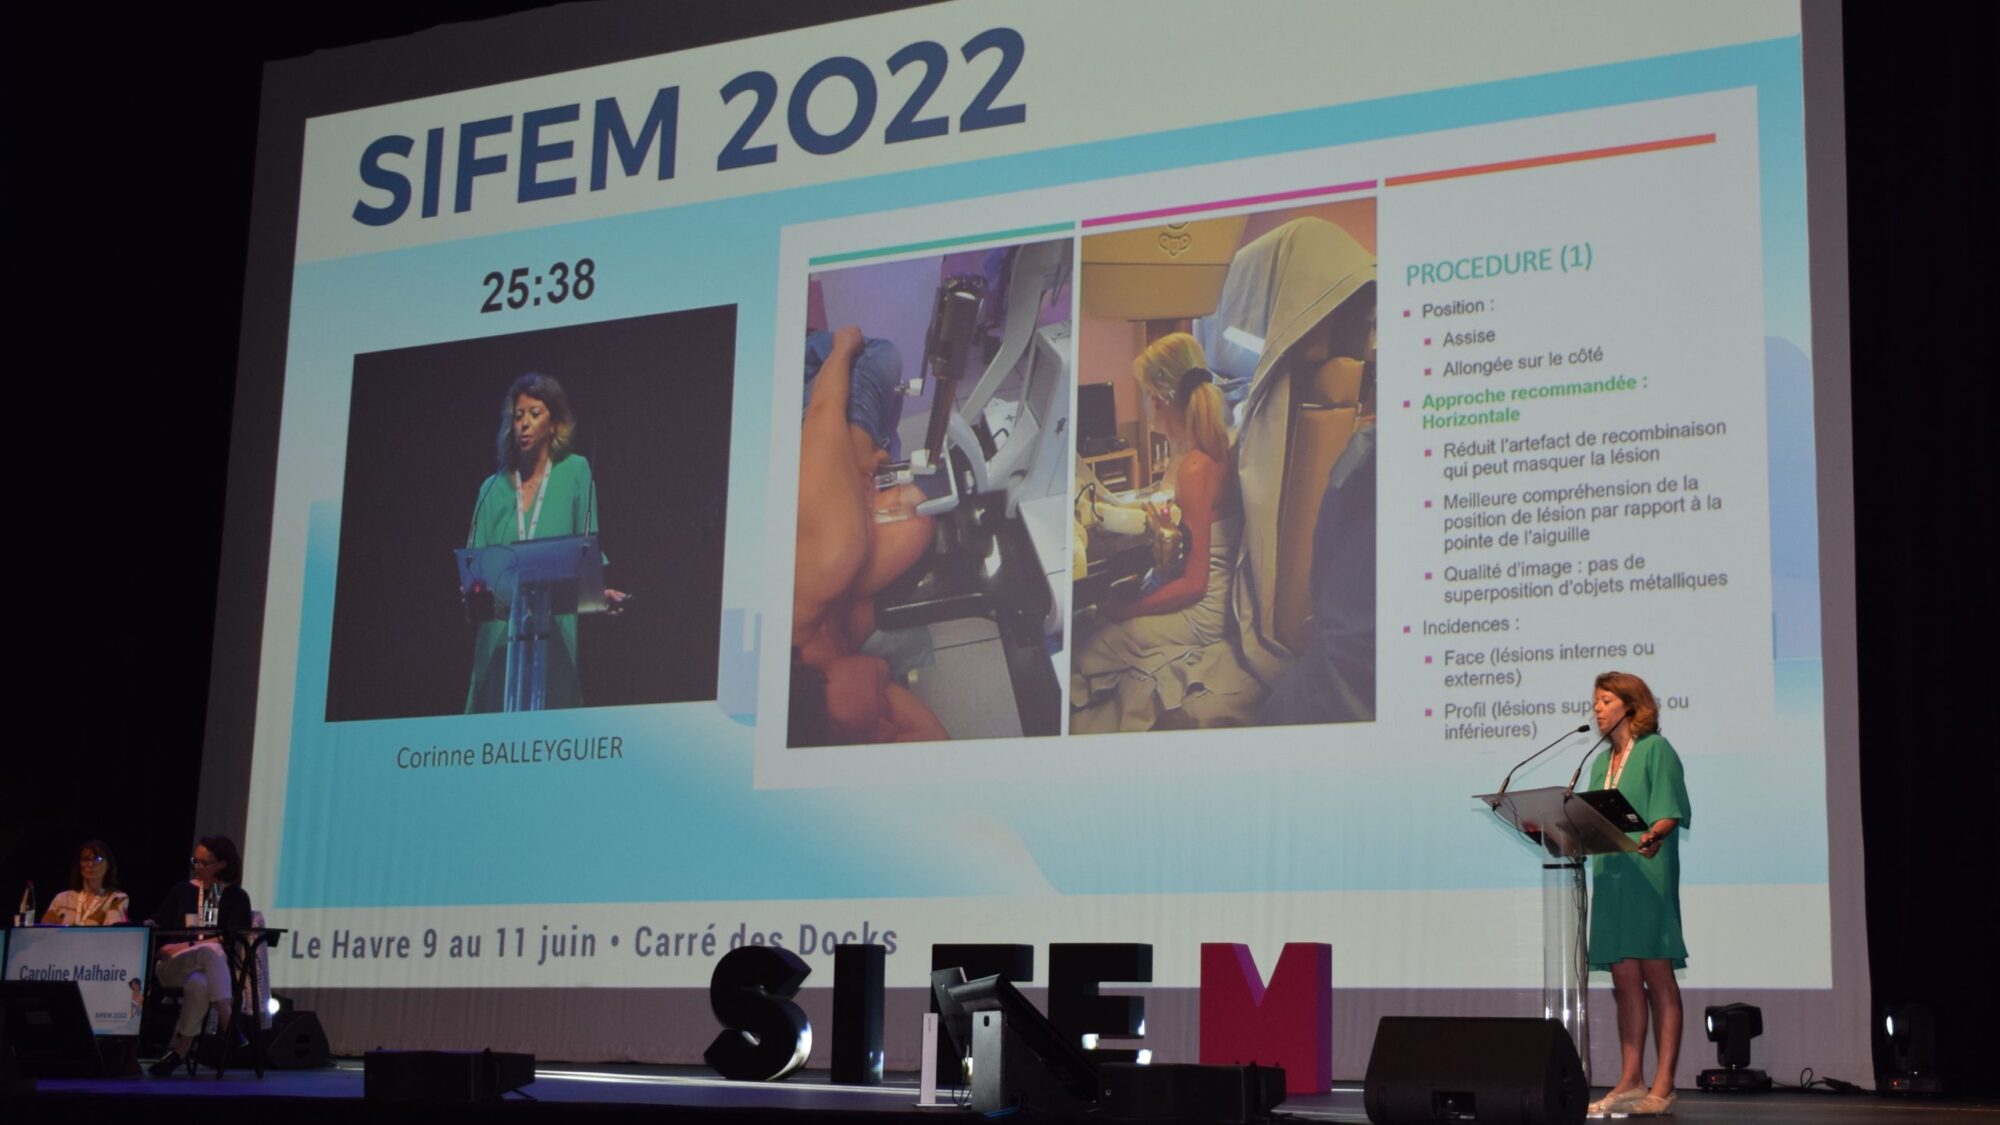

Le 10 juin, le congrès de la Société d'imagerie de la femme (SIFEM) a consacré une session à l’angiomammographie. Corinne Balleyguier, cheffe du service d’imagerie médicale du centre de lutte contre le cancer Gustave-Roussy, à Villejuif (94), a partagé l’expérience de sa structure des biopsies sous angiomammographie. « C’est une technique qui se développe et rend beaucoup de services, surtout dans des bilans rapides, avance-t-elle. À ce jour, 400 procédures de biopsie sous angiomammographie ont été réalisées sur 30 sites dans le monde. »

Première mondiale

La première biopsie sous angiommamographie au monde a été réalisée au centre Gustave-Roussy en octobre 2019. « Cette technique reprend le principe de la biopsie guidée sous IRM, c’est-à-dire que l’on a une angiomammographie de référence qui met en évidence des prises de contraste suspectes, indique l’intervenante. À partir du moment où on ne les a pas retrouvées sur les clichés complémentaires de mammographie ou d’échographie, on refait